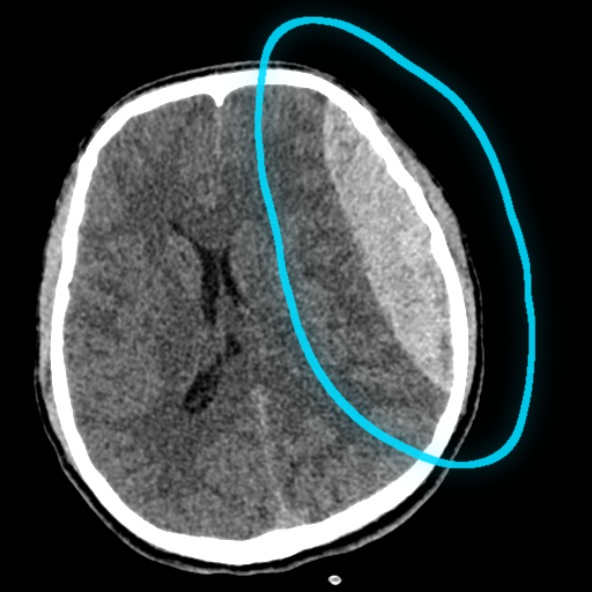

Puzzle 53 annotated

What's the Diagnosis?